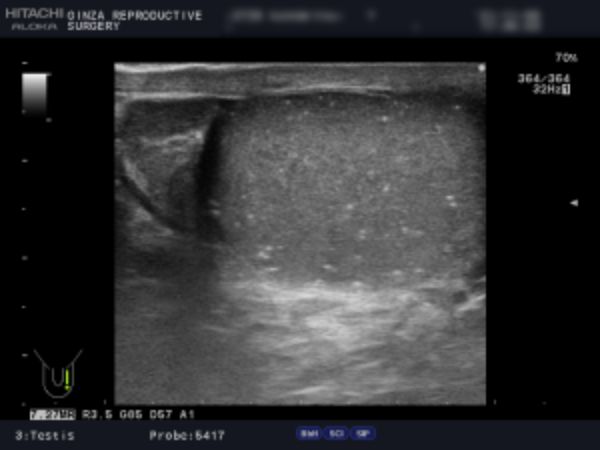

精索静脈瘤の検査は「触診」「エコー検査」によって行います。

精索静脈瘤はその重症度を「グレード」で表します。視診・触診でも度合いを判断することはできますが、正確なことはエコー検査でしか診断することはできません。

軽症の場合、手術の必要はありませんが、当院では診察で「グレード3(見てわかる:陰のうが凸凹している、腫れている)」「グレード2(触ってわかる:腫れている)」、エコー検査で精巣周辺の静脈の太さ3mm以上が複数または2.8mm以上が多数あるものを手術適応としています。

検査は、視診と触診の他、エコー検査で精巣周囲の静脈の太さを確認します。

陰嚢専用の機器を用いてエコー検査を行い、陰嚢の状態を検査します。正確に検査することで的確な手術ができ、再発の可能性を限りなく下げることができます。

エコー検査では、精巣腫瘍、精液瘤、精巣水腫、精巣内石灰化の有無などを確認します。